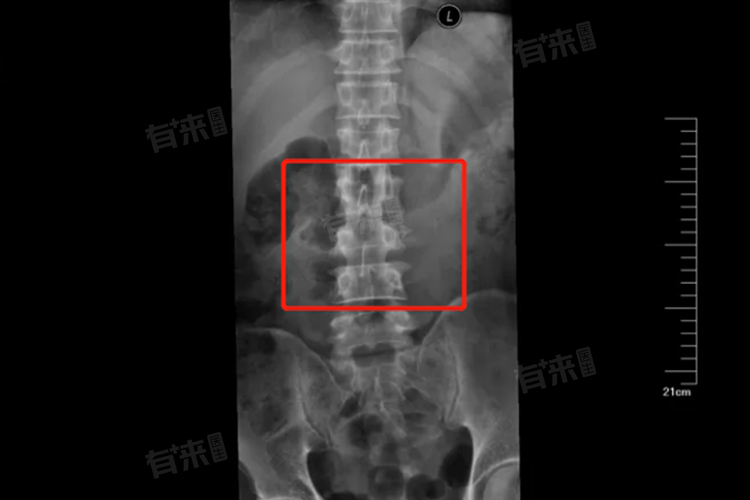

- 但是如果骨折出现了明显的移位,或者是粉碎性骨折,就比较严重了。移位的骨折可能会对周围的肌肉、神经等组织造成压迫和损伤,引起更剧烈的疼痛、肌肉无力甚至感觉异常等症状。粉碎性骨折则意味着骨折的复杂性增加,恢复起来会更加困难,需要更长的时间和更精细的治疗。